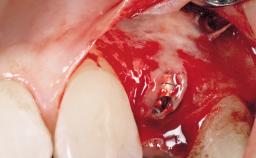

Late Placement of an Implant in a Maxillary Left Central Incisor Site

Bone Volume | Deficient horizontally, requiring prior grafting |

Risk of Complications | Moderate |